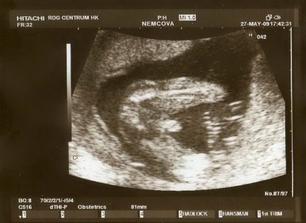

Nová naděje. Bohužel to bylo opět stejné, jako již dvakrát předtím. Třetí revize, třetí ztráta naděje. Jsem po laparoskopii a hysteroskopii a čekáme na výsledky imunologie v Plzni. Pak se uvidí co dál. V únoru 2009 nám v Sanusu doporučili ještě dva měsíce domácího snažení. Tak jsme se snažili a nyní napjatě sledujeme čárku. HCG nám krásně stoupá, 20. den po ovulaci je 2066. Máme 1. fotku dutinky. Přes nejrůznější potíže a patnáctidenní hospitalizaci nám miminko krásně roste. 22. dubna konečně po čtrnácti dnech ukázalo nosánek, máme nosní kůstku, NT je 2,0. Máme vše, co máme mít a rodiče se dnes poprvé společně dívali na ultrazvuk. Viděli mě i 4D, to koukali. Odnesli si video a teď na něj pořád koukají. Další kontrola náš čeká 5. května, opět ultrazvuk, triple testy a poradna. Trošku změna situace, mamka se mnou leží od 27. dubna v nemocnici, ale já ji dělám radost, rostu, 16.6. už vážím 360 gramů a od 5.6. ji kopu a ona o tom ví. Od 10. 6. se nám začal malinko měnit nález až jsme museli 10. 7., gr. h. 24+2 na cerclage, potom jsme měli zánět ledvin a astmatický záchvat. Pořád mamce tvrdlo břicho, tak se bez infuzí neobejde. 18. 7. se ještě objevilo krvácení, ale nebylo to nic závažného, byli jsme na ultrazvuku a vážím 908 gramů. V pátek 24.7. se to zlepšilo a kapeme na nejnižší rychlost, hurá. Mamka zatím nesmí chodit, má to slíbeno na 2. září. Kapeme sice na nejvyšší rychlosti, ale na ultrazvuku 4.8. mám odhad 1280 gramů. Dne 18.8. jsme byli na ultrazvuku a mám odhad 1750 gramů, mám trochu víc plodové vody a tak si tam plavu jako v bazénku. Dne 28.8. jsme byli s mamkou zase na ultrazvuku, vážím už 1950 gramů, mám udělaný krásný 3D fotečky, vody už nemám tolik moc, tak je mamka ráda. Jen se nám zase zkrátil čípek, už mě tam drží jen steh a 13 mm, ale držím mamce pěstičky, aby jsme vydrželi. No a taky si musím zvykat, mamka totiž má už dovoleno chodit na wc, a já jsem byl zvyklej, že pořád leží. Je sice z toho unavená, ale šťastná. Já jsem jí ještě udělal radost, že jsem se přetočil hlavičkou dolů. Dne 1.9. se mi konečně podařilo zbavit se té nitě, co tam mamka měla. Všichni jsou překvapení, jak se to mohlo stát, ale steh je pryč. Dne 10. 9. jsme s mamkou byli zase na ultrazvuku, vážím 2368 gramů (33+1). Hrdlo máme sice jen 9 mm, ale já se tam ještě udržím! Plodové vody mám už akorát, mamce klesly jaterní testy, žlučové kyseliny jsou v normě, tak má radost. Tak dnes 17. 9. jsem se byl zase vážit, mám 2517 gramů. Hrdlo má mamka jen 6,7 mm s obrovitým funnelingem, ale pořád drží. Denně mi točí monitory, mám je vzorné a pořád nemůžu přijít na to, jak ty sondy odkopnout. 26.9. pustil pan doktor mamku na propustku, byla poprvé 12 hodin mimo nemocnici, byli jsme na zahradě, grilovali jsme a já jsem babičce, dědečkovi a strejdovi předváděl, jak umím krásně kopat. Mamka byla moc šťastná. Večer se vrátila do nemocnice, dala si po 23. hodině sprchu a když usínala, tak jsem ji hodně překvapil, vypustil jsem svůj bazén. A tak se nešlo spinkat, ale na porodní sál. Šlo to pěkně a přesně ve 4.00 hodin jsem se narodil za skvělé asistence mého tatínka, který mamince na sále moc pomáhal. Vážím 2740 gramů a měřím 50 cm. Dosáhl jsem gestačního stáří 35+4. Rodiče a velká spousta lidí kolem ze mě mají velikánskou radost. Trošku jsem odmítal v inkubátoru dýchat, tak mě 1 den pomáhal CPAP. Večer mi ho vzali a teď už se snažím sám. mamka za mnou chodí a já jsem rád, když ji vídím. Dnes jsem na ni poprvé otevřel očička, snažím se papat, dnes už ze stříkačky. Tatínek je ze mě unešenej a já jsem rád, když mě přijde pohladit a vyfotit.